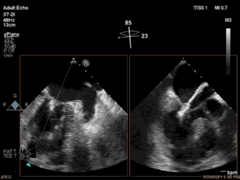

3月30日患者先在全麻下进行TEE(经食道超声心动图)再次评估瓣膜情况(视频4、视频5、视频6 ),确定为二尖瓣前组乳头肌断裂致二尖瓣前瓣脱垂并重度返流,其脱垂部位、瓣叶结构、瓣口面积等适合进行二尖瓣夹合术。术中IABP辅助,ECMO湿备,穿刺右侧股静脉,在TEE指导下顺利穿刺房间隔,随后送入二尖瓣夹合系统,在超声指导下于二尖瓣A2/P2区植入一枚Mitraclip XTR夹合器(视频7),术后TEE评估返流程度从5+降至1+(视频8 ),夹合结果满意,二尖瓣呈双孔启闭(视频9 ),术后二尖瓣平均跨瓣压差1mmHg(图1),收缩期肺静脉返流消失(图2 ),手术总耗时80min。香港亚洲医疗中心林逸贤教授通过视频连线进行手术全程技术支持。

视频4

视频5

视频6